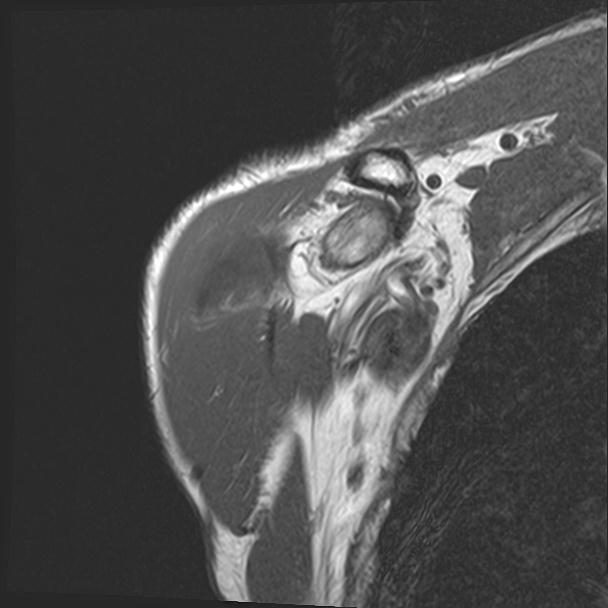

60058 3/9 11/4 右肩 2R+MRI 73歳男性 肩腱板損傷